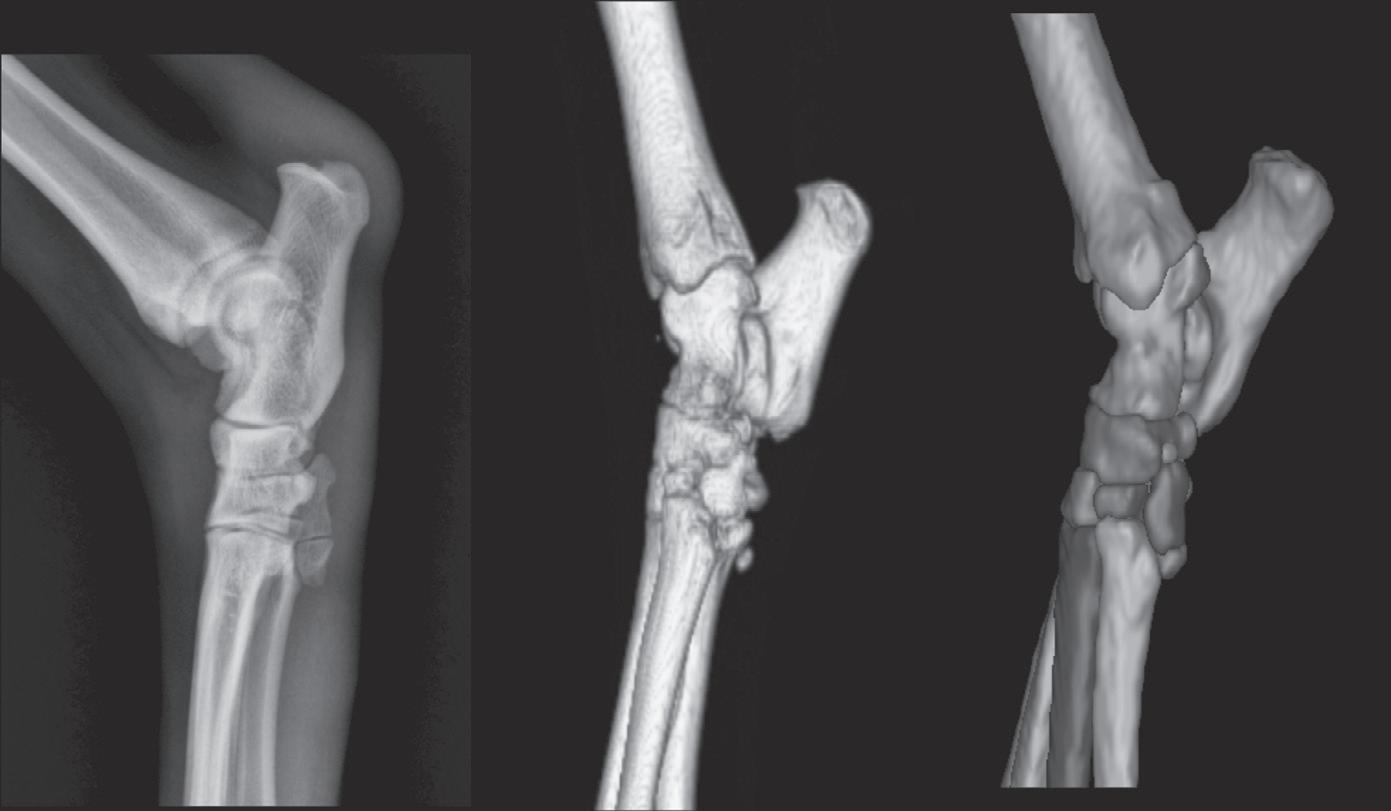

Figure 1-5. Correct orientation of a sagittal-plane radiograph of an extremity. A caudocranial view of a humerus is shown here. There is no convention regarding whether the lateral side of the limb is placed on the examiner’s right (A) or left (B). However, it is probably more common to orient medial and lateral relative to the patient. As such, a left limb would be oriented as in Figure 1-5A, and a right limb would be oriented as in Figure 1-5B.